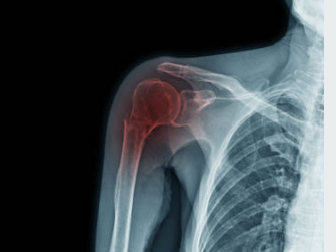

회전근개 파열 수술 후 회복기간

회전근개 파열 수술은 내시경 수술로 진행됩니다. 내시경 수술은 작은 구멍을 통해 카메라와 수술기구를 삽입하여 수술하는 방법입니다. 이 방법은 큰 상처가 없고, 출혈이 적고, 회복이 빠릅니다. 수술 방법은 파열된 힘줄을 다시 붙여주거나, 재배치하거나, 재건하는 방법이 있습니다. 수술 시간은 1~2시간 정도 걸립니다.